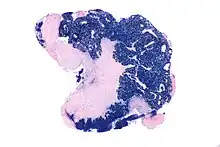

| Micrograph showing a nasopharyngeal carcinoma positive for Epstein-Barr virus-encoded small RNAs (EBER). | |

Undifferentiated nasopharyngeal carcinoma—low power

Undifferentiated nasopharyngeal carcinoma—low power Undifferentiated nasopharyngeal carcinoma—med. power